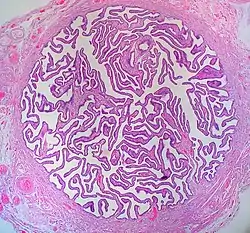

![]() Cross-section of Fallopian tube, stained and viewed under microscope | |

When viewed under the microscope, the Fallopian tube has four to five layers (depending on the classification system used). From outer to inner, these are the serosa, subserosa, muscularis, submucosa and innermost mucosa with lamina propria, and epithelium. The serosa is derived from the visceral peritoneum. The subserosa is composed of loose adventitious tissue, blood vessels, lymphatics. The muscularis consist of outer longitudinal and inner circular smooth muscle coats. This layer is responsible for the rhythmic contraction, called peristalsis, of the Fallopian tubes.[7] The histological features of tube vary along its length. The mucosa of the ampulla contains an extensive array of complex folds, whereas the relatively narrow isthmus has a thick muscular coat and simple mucosal folds.[7]